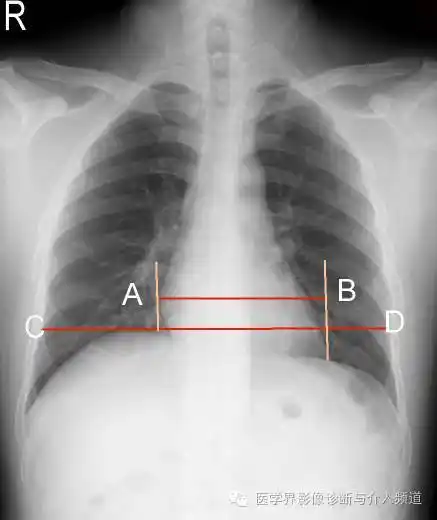

手把手教你阅读平片之胸部平片

全面解密:正确的,正常的,胸部正位片!

胸部x线,这么看你简单多了